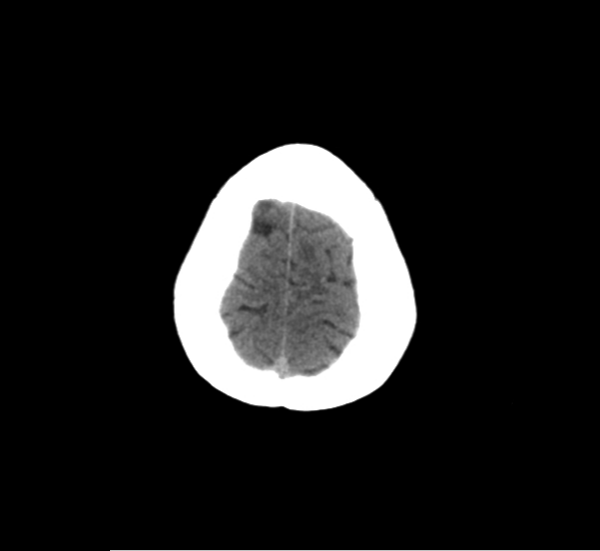

CT Brain Anatomy